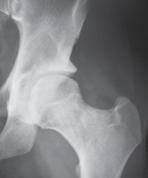

a. Vad är en s k CAM-lesion? (1p)

b. Vilka symtom kan en patient ha med en sådan lesion? (1p)

c. Vilka är de röntgenologiska undersökningsfynden? (1p)

a. CAM-lesion kan vara en orsak till femuroacetabulär impingement (FAI) där man har en påbyggnad på collum femoris främre övre omfång.

b. Symtom kan vara höftsmärta och inskränkt rörlighet, ssk flexion men även inåtrotation och adduktion.

c. På slätröntgen eller CT, alternativt MR ses ”Pistol-grepps-deformitet”, benpåbyggnad vid övergång superiort mellan caput-collum och förlust av sfäriciteten av caput femoris.